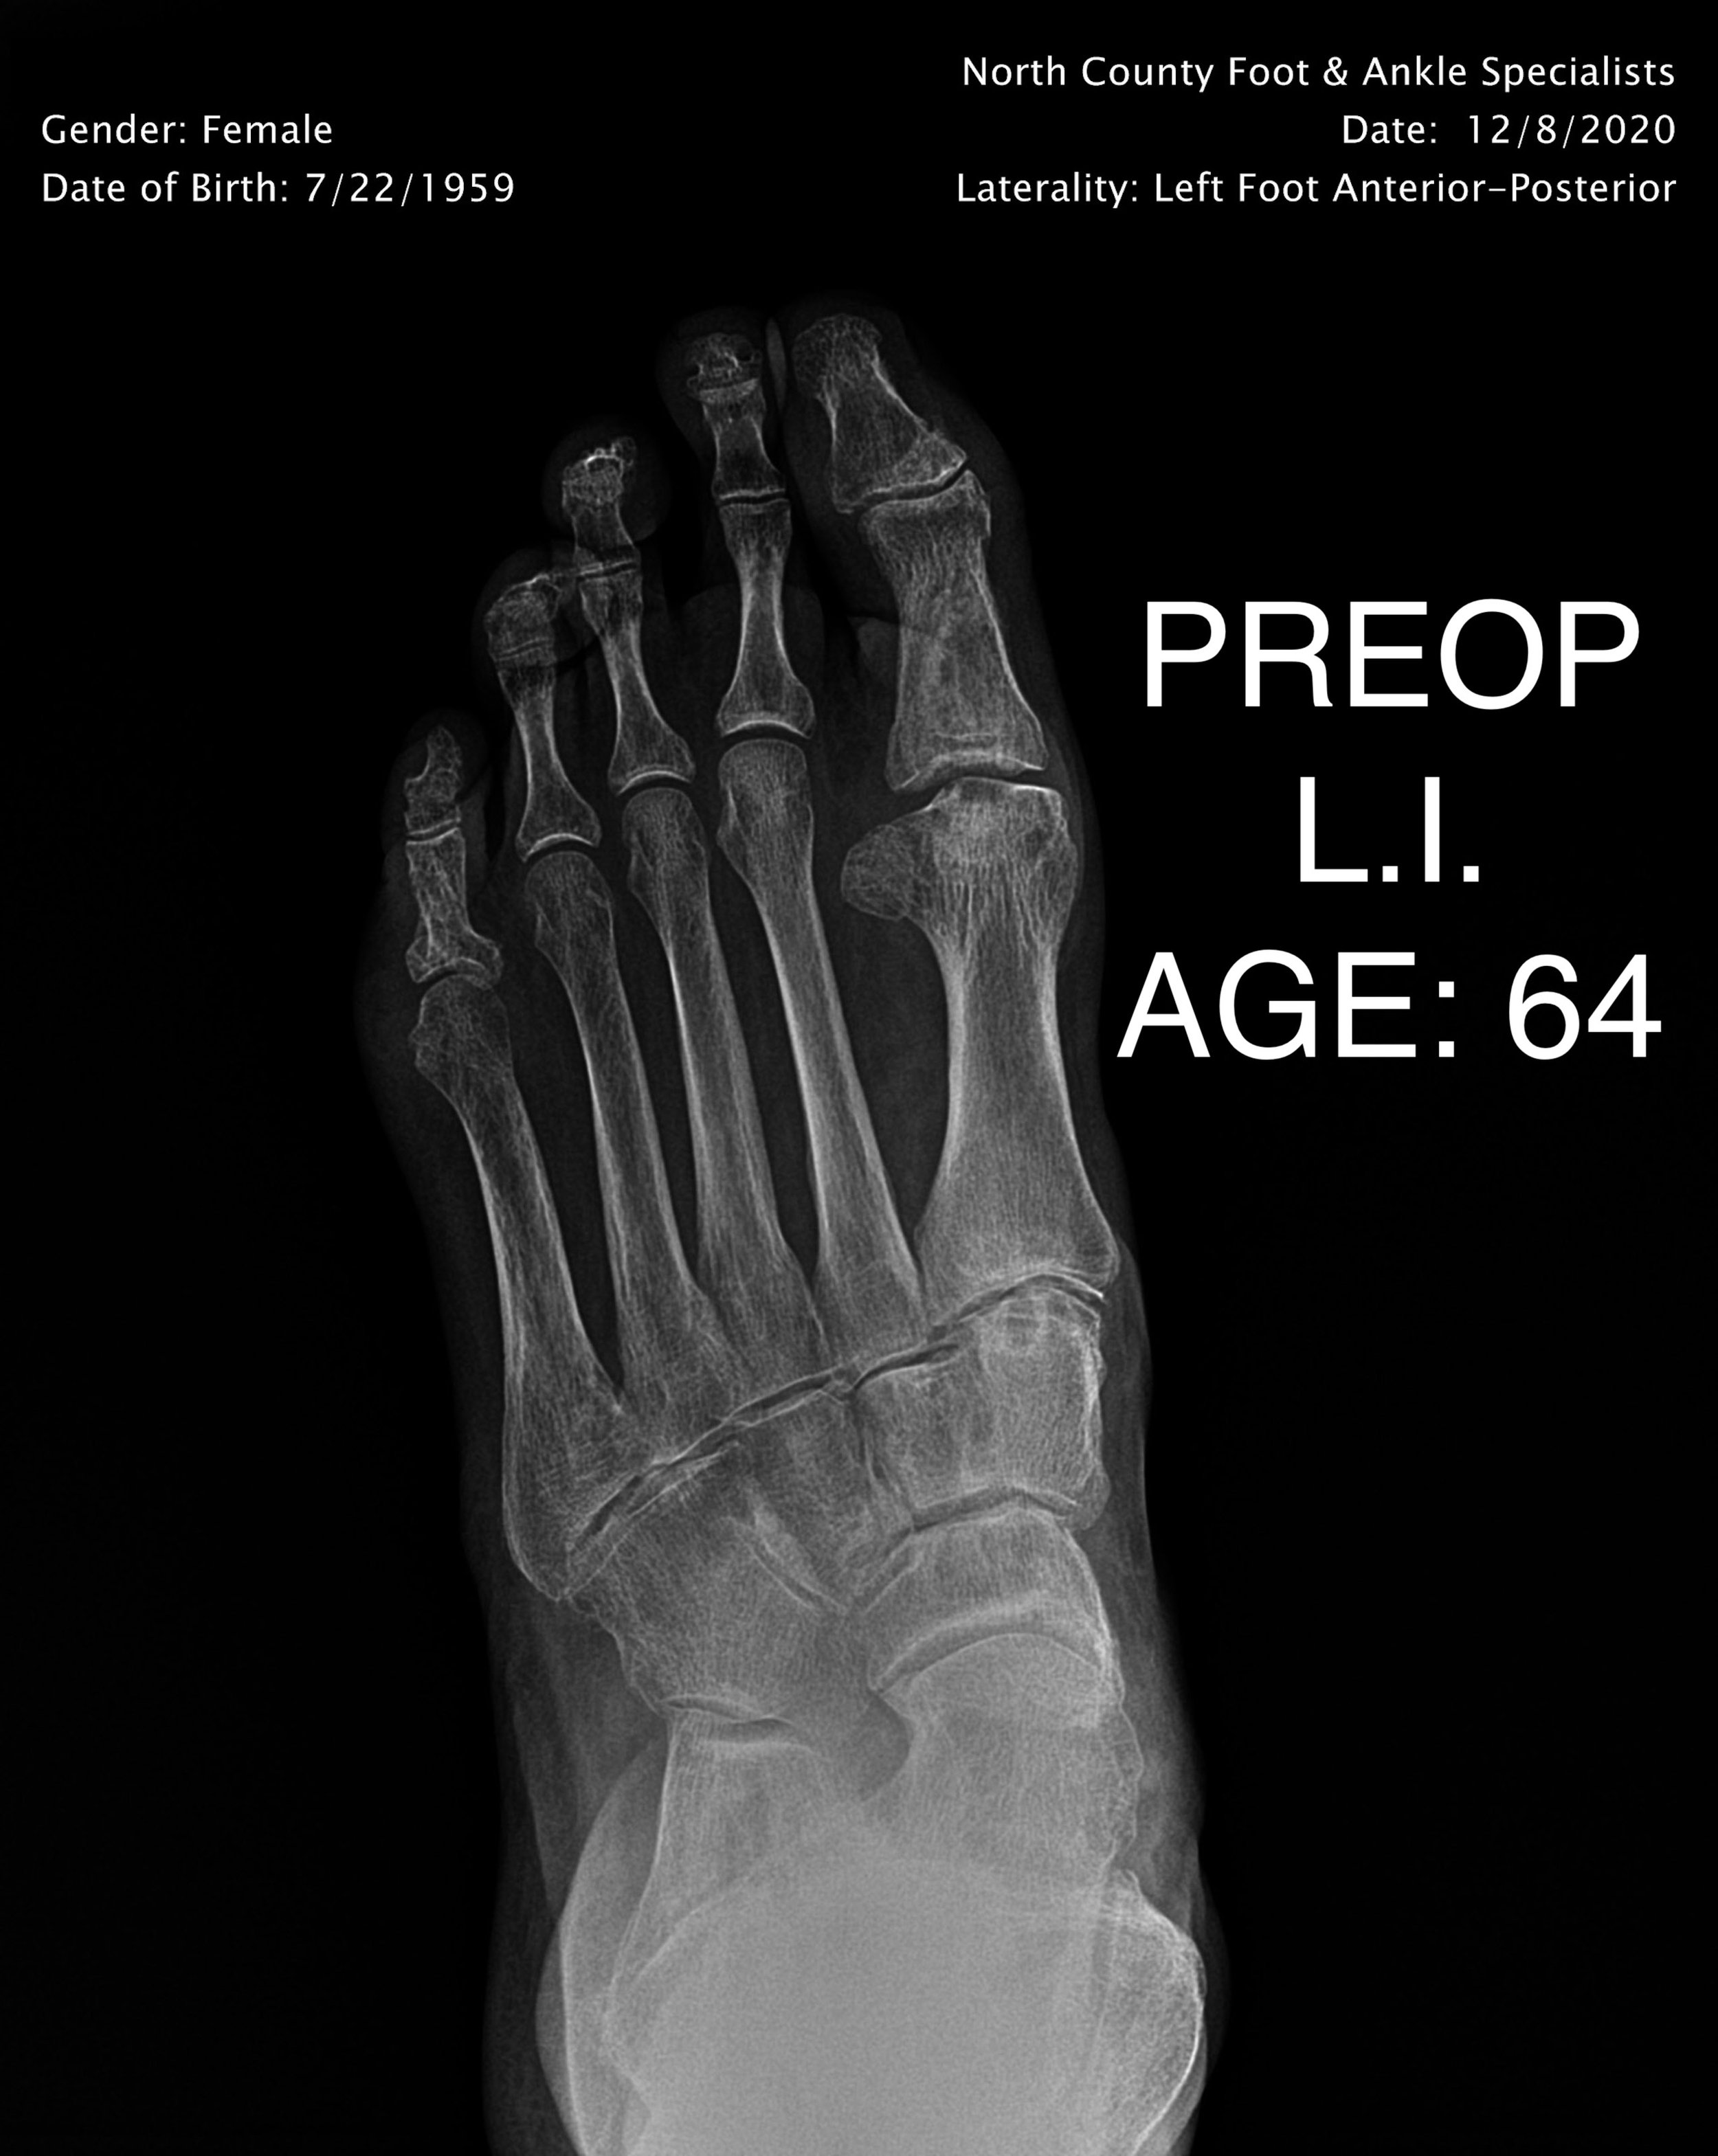

ADULT FLAT FOOT RECON